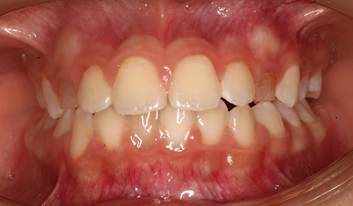

Figura 17. Mejora de la dimensión vertical dental.

Logramos determinar cómo el uso de los espolones logró corregir el hábito de la deglución atípica para así mejorar la dimensión vertical dental.